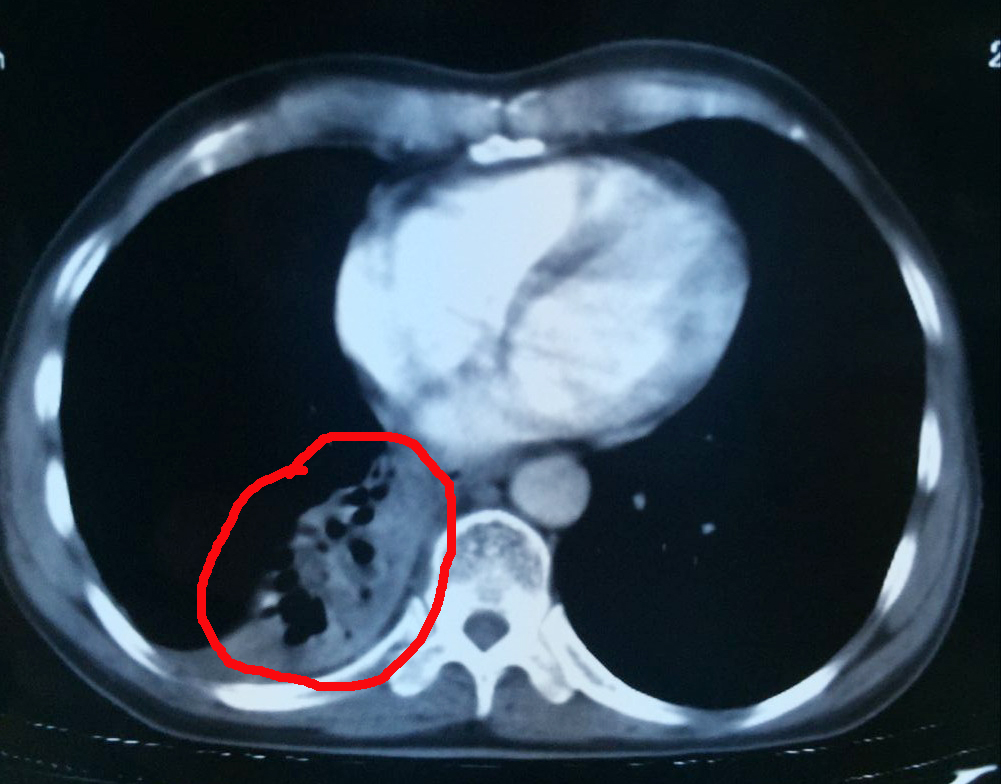

腫瘤治療中